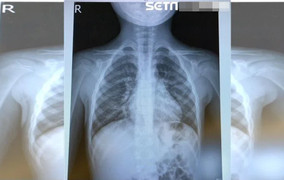

Bệnh lây truyền qua đường hô hấp thường gia tăng theo mùa. (Ảnh minh hoạ)